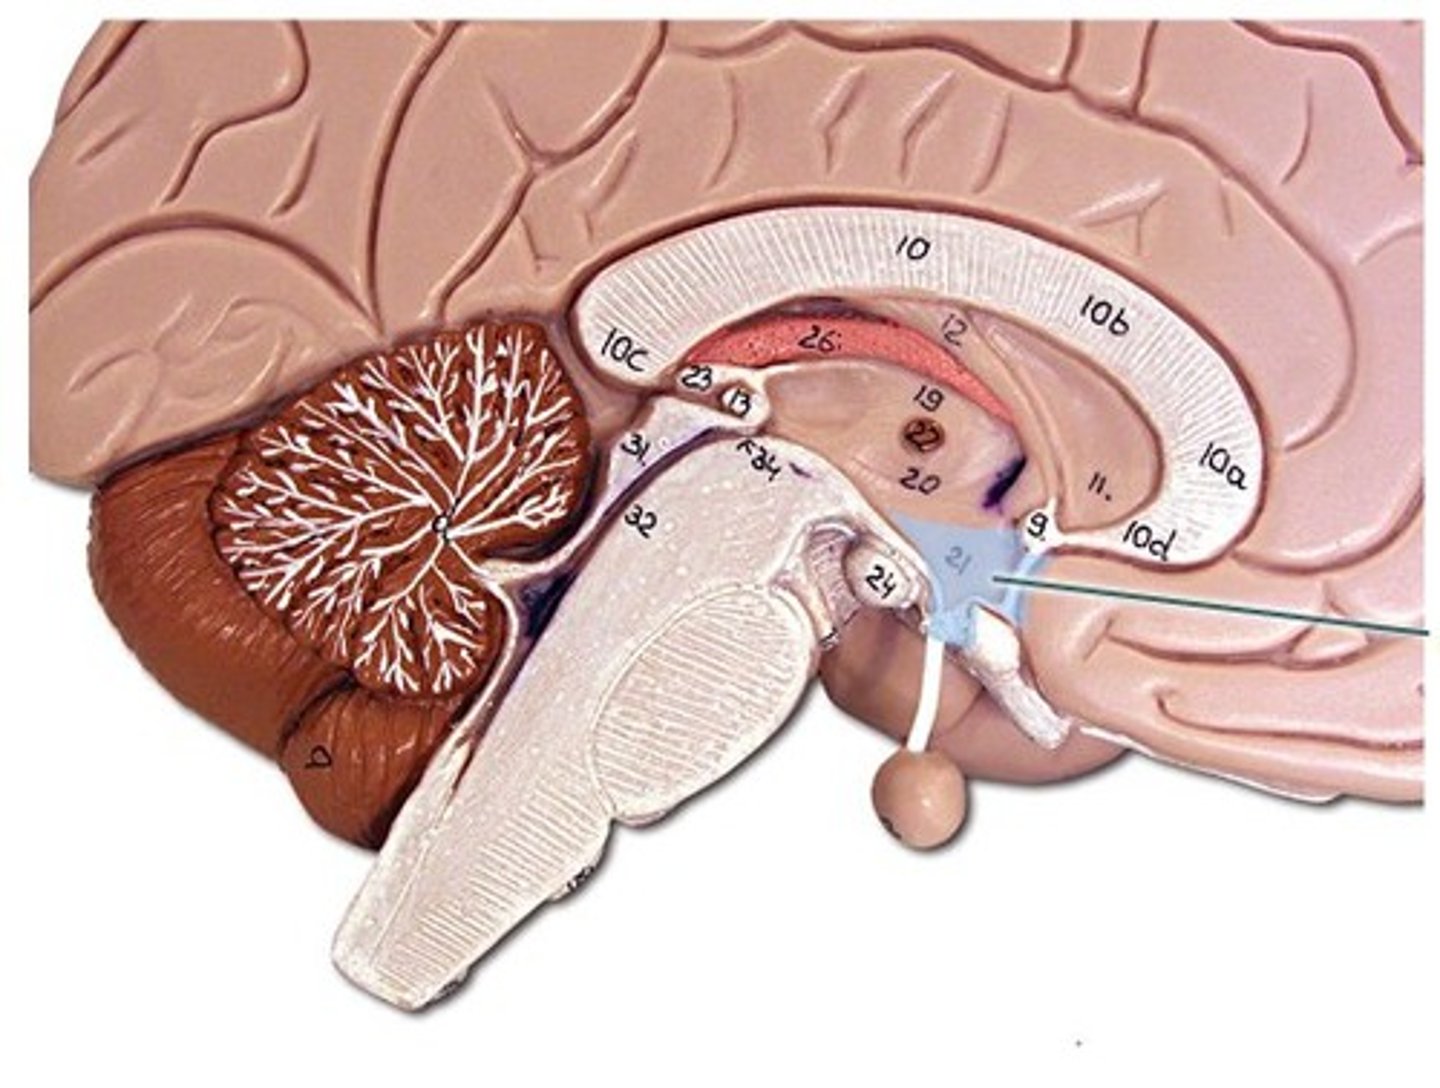

corpus callosum

A thick band of axons that connects the two cerebral hemispheres and acts as a communication link between them.

Diencephalon

central part of the brain made up of the thalamus, hypothalamus, and epithalamus

thalamus

•Oval masses of gray matter on lateral sides of third ventricle

•“Relay center” - Receives signals from all conscious senses except olfaction and relays some signals to appropriate part of cortex and filters out other signals distracting from subject of attention (for example, background noise in crowded room)

hypothalamus

a neural structure lying below the thalamus; directs eating, drinking, body temperature; helps govern the endocrine system via the pituitary gland, and is linked to emotion

pituitary gland

endocrine gland at the base of the brain

cerebellum

the "little brain" at the rear of the brain; functions include processing sensory input and coordinating movement output and balance

arbor vitae

white matter of the cerebellum